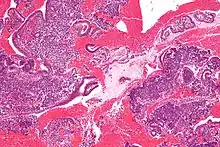

(A) proliferative endometrium (Left: HE × 400) and proliferative endometrial cells (Right: HE × 100)

(B) secretory endometrium (Left: HE × 10) and secretory endometrial cells (Right: HE × 10)

(C) atrophic endometrium (Left: HE × 10) and atrophic endometrial cells (Right: HE × 10)

(D) mixed endometrium (Left: HE × 10) and mixed endometrial cells (Right: HE × 10)

(E): endometrial atypical hyperplasia (Left: HE × 10) and endometrial atypical cells (Right: HE × 200)

(F) endometrial carcinoma (Left: HE × 400) and endometrial cancer cells (Right: HE × 400).